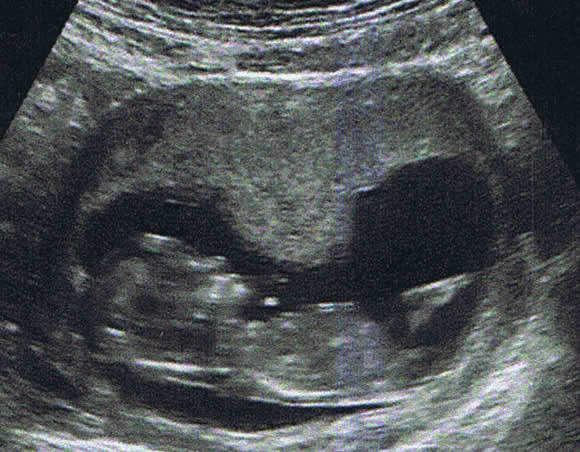

P’TIT BOUT….

Et voilà un nouveau venu dans la famille ….

Il est seul finalement mais à l’air en pleine forme. Vivement la fin de l’année pour voir notre bébé en vrai….